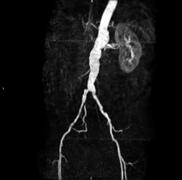

June 4, 2010 – The first national contract signed for a magnetic resonance imaging angiography (MRA) contrast agent was been signed, making it available to more than 27,000 medical facilities. The contract with Amerinet Inc., a leading national health care group purchasing organization, gives access to Ablavar (gadofosveset trisodium), an injectable MRA blood pool imaging agent indicated to evaluate aortoiliac occlusive disease (AIOD) in adults with known or suspected peripheral vascular disease (PVD).

The agent helps produce high-resolution images and is uniquely designed for vascular imaging, making it possible for physicians to detect vascular disease less invasively than with conventional X-ray angiography. Additionally, the product requires no radiation or iodine and can provide both first pass and blood pool images with a single, low dose injection.”

Blood pool agents remain in the vasculature for an extended period of time, increasing the brightness of blood, resulting in high-resolution images. The albumin-binding properties of Ablavar make it uniquely designed for vascular imaging because it provides an expanded imaging window, making it possible to evaluate not only the location of disease but also the extent and severity of disease.

The agent was cleared for use in the United States in January and is the first and only blood pool contrast agent approved for magnetic resonance angiography to evaluate peripheral artery disease (PAD).